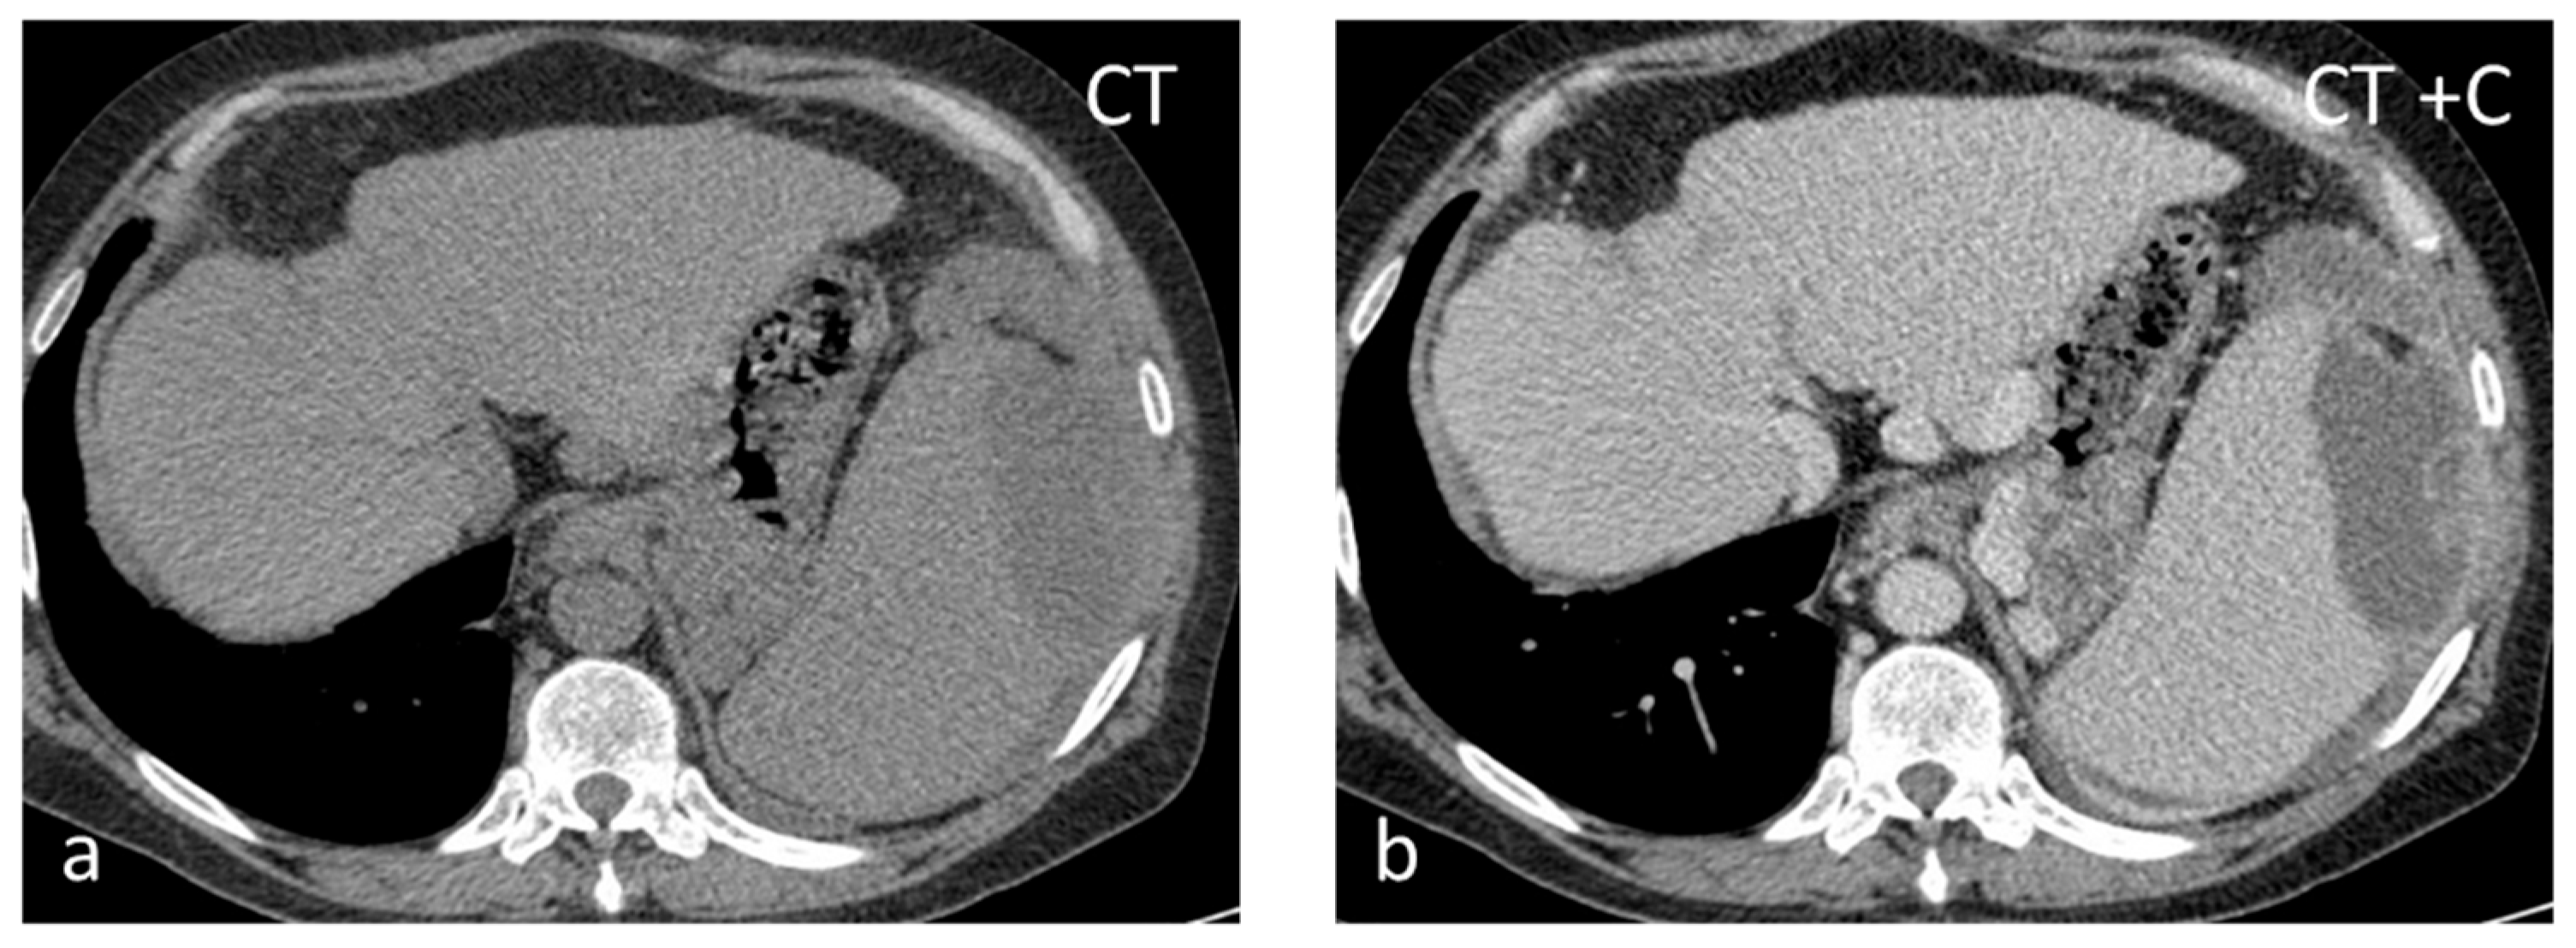

Sarcoidosis is a multisystem disease characterized by the presence of non-caseating granulomas. One-third of patients presenting with splenic sarcoidosis findings have normal chest radiography [18]. Splenic involvement has been reported in about 40% of cases of multisystem sarcoidosis, but isolated sarcoidosis of the spleen is extremely rare [19]. It may present either as splenomegaly or with multiple nodules, whereas a solitary splenic lesion is very rare. Patients with diffuse splenic granulomas have a worse prognosis in terms of persistent chronic sarcoidosis than patients without splenic involvement or patients with limited splenic disease [20]. Nodules appear hypodense on CT and have low SI both on T1-WI and T2-WI, with minimal delayed enhancement [21] (Figure 2). Nodules are best seen on T2-WI with fat saturation and on early gadolinium-enhanced T1–WI. MRI is said to be able to monitor disease activity, as during active inflammation, nodules demonstrate T2-WI hyperintensity due to edema and high vascular permeability, as well as restricted diffusion [22]. The main differential diagnosis includes infections, especially tuberculosis, and malignancies, especially lymphoma. The final diagnosis is based on three main criteria: a compatible presentation, the evidence of non-caseating granulomas on histological examination, and the exclusion of any alternative diagnosis [23].

Figure 2.

Sarcoidosis. US shows multiple hypoechoic nodules (a). The nodules appear slightly hypointense on T2 WI (b) and show mild delayed enhancement (c,d).